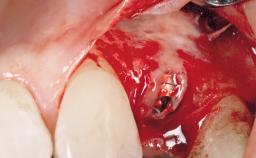

Placement Protocol Immediate implant placement

Socket Morphology Single-root socket

Socket Integrity Sufficient, with intact bone walls

Bone Volume Sufficient, with intact walls

Bone Augmentation Horizontal|Simultaneous

Augmentation Materials Autogenous chips|Membrane